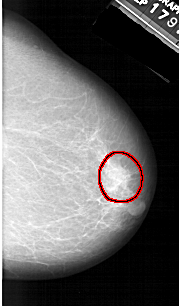

A_1309_1.RIGHT_CC

RIGHT_CC LINES 4891 PIXELS_PER_LINE 2851 BITS_PER_PIXEL 12 RESOLUTION 43.5 OVERLAY

FILE: A_1309_1.RIGHT_CC.OVERLAY

TOTAL_ABNORMALITIES 1

ABNORMALITY 1

LESION_TYPE MASS SHAPE IRREGULAR MARGINS ILL_DEFINED

ASSESSMENT 4

SUBTLETY 4

PATHOLOGY BENIGN

TOTAL_OUTLINES 1

BOUNDARY